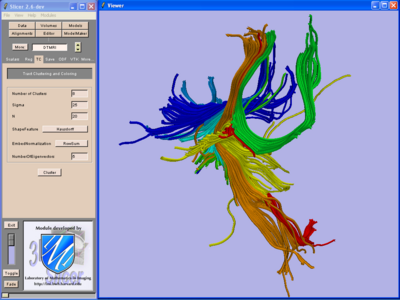

We are developing tools in the 3D Slicer for automatic clustering of tractographic paths through diffusion tensor MRI (DTI) data. By grouping tractographic paths based on shape and location, the white matter architecture may be more clearly visualized, and interesting properties of the clusters (such as for example FA or Westin's linear measure) may be quantified.

Clustering Implementation

Our implementation uses spectral clustering, a method for grouping data using eigenvectors of a data affinity matrix. This image gives an overview of the method. On the left example input tractographic paths are shown (these were created by manually seeding in the 3D Slicer). The center image shows an embedding of the tracts as points in 2D, where the distance between points is related to their shape similarity. This embedding was calculated as an intermediate step during spectral clustering. The image on the right shows the final output in the 3D Slicer, where tractographic paths are colored by cluster membership.